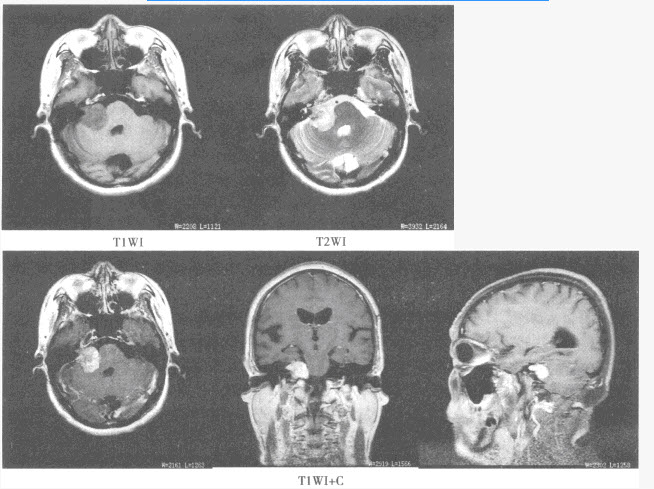

患者,女,50岁,因头晕半年来院检查,影像检查如下图。

A.星形细胞瘤

B.少突胶质细胞瘤

C.室管膜瘤

D.脑膜瘤

E.转移瘤

F.脑囊虫病

A.脑膜尾征

B.钙化

C.均匀强化

D.发病部位

E.周围水肿明显

F.以上都不是